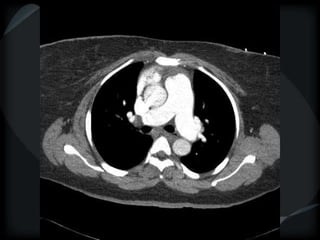

PHTN – PA 39mm

39.2mm

PHTN and septal thickening

? PVOD